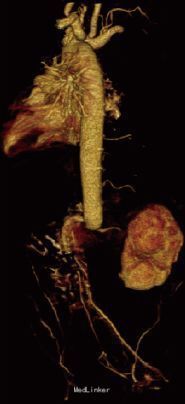

T 37.2℃,P 126次/min,R 62次/min,BP 88/56mmHg。神清,皮肤黏膜无出血点、瘀斑,前囟平软,1.5cm×1.5cm,呼吸稍促,三凹征阴性,双肺呼吸音粗,闻及少许痰鸣音,心前区无隆起,心率 126次/min,心前区闻及Ⅱ/6级收缩期杂音。下肢肢端稍凉,CRT<2s。心脏彩超:卵圆孔未闭。腹主动脉超声:腹主动脉近肾动脉水平内可见实质性低回声充填,内未见明显血流信号,双侧髂外动脉血流速度约15cm/s,呈阻塞性频谱。腹部增强CT示:左肾动脉平面以下腹主动脉、髂总动脉未见显影,考虑为动脉栓塞可能。

诊断:1.腹主动脉血栓 2.新生儿缺氧缺血性脑病 入院后予苯巴比妥止惊、抗感染、营养心肌、营养神经等对症支持治疗。入院第3天患儿抽搐止,双上肢肢端肤色红润、皮温正常、CRT正常,双下肢肢端肤色苍白、皮温低、CRT延长,双上肢血压高于双下肢,血压差异超过20mmHg。家属放弃治疗,未行抗凝、溶栓等治疗,未规律随访。